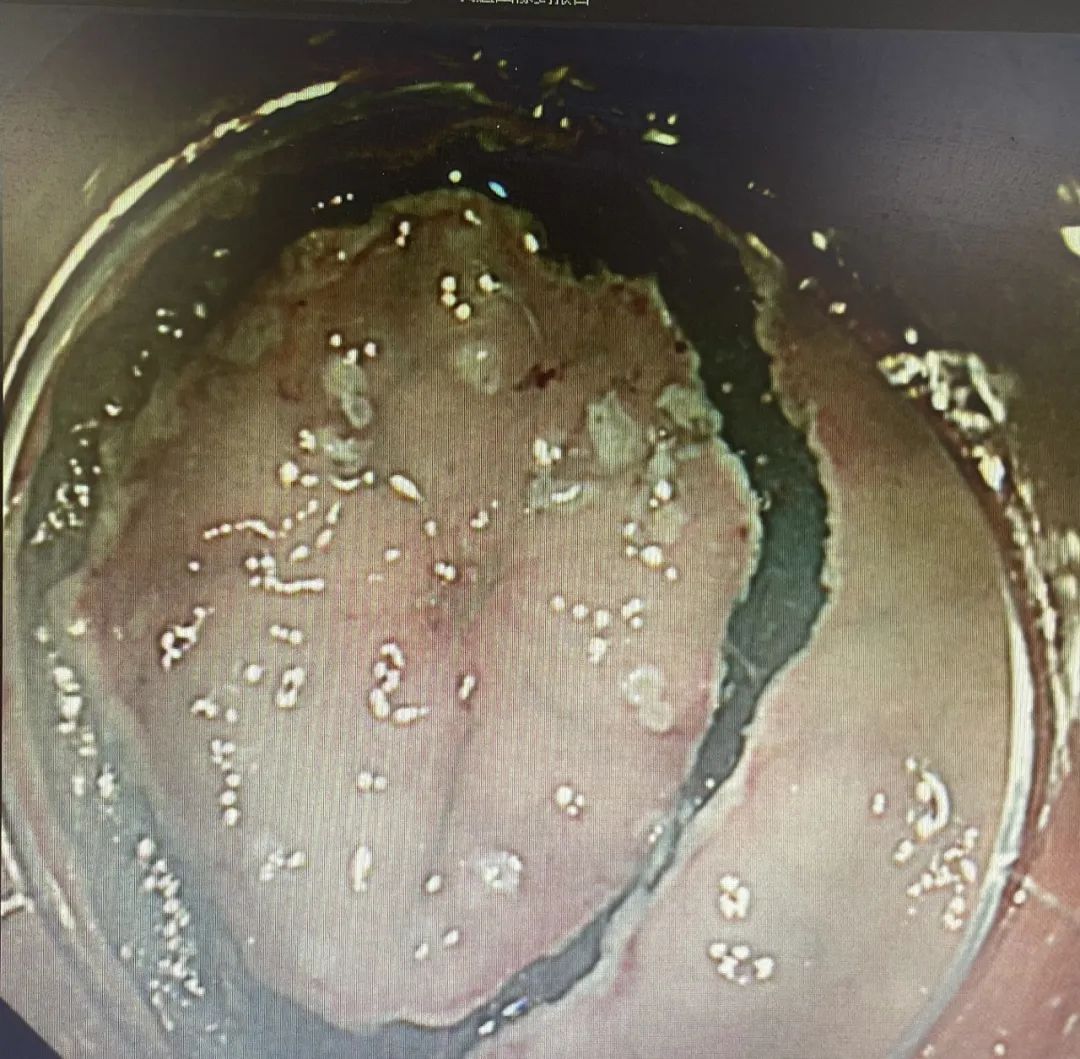

患者,67岁,近一个月因腹部疼痛到院行胃肠镜检查,胃镜提示胃体小弯糜烂性病变,贾傲主任提取组织活检,病理提示高级别上皮内瘤变、局部癌变。根据检查结果诊断:胃恶性肿瘤,行无痛胃镜下内镜黏膜下剥离术(ESD)。

患者,78岁,因“腹部不适”到院行胃肠镜检查,胃镜下显示为萎缩性胃炎,贾傲主任高度怀疑这是一个早期胃癌,根据经验提取组织活检,病理提示粘膜组织部分腺体上皮高级别上皮内瘤变,考虑灶状癌变。跟家属充分沟通后,行无痛胃镜下内镜黏膜下剥离术(ESD)。

患者,60岁,因“便血一周,时有反酸”到院行胃肠镜检查,结合病理提示(胃窦粘膜)高级别腺上皮病变。无特殊禁忌,于是行无痛胃镜下内镜黏膜下剥离术(ESD)。